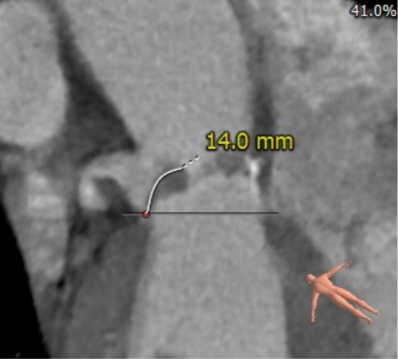

患者男性,70岁,重度钙化型主动脉瓣狭窄,STS评分8.6%,常规外科手术高风险。术前心脏超声提示主动脉瓣严重增厚钙化,峰值流速5.4m/s,平均跨瓣压差82mmHg。CT评估结果显示主动脉瓣重度钙化,瓣环平均直径23.9mm,瓣环面积448.4mm²。左冠脉开口高度8.5mm,右冠脉开口高度12.2mm。该患者左、右冠状动脉开口高度低,左冠瓣叶较长伴钙化,且瓦氏窦较小,窦管交界处高度低,冠状动脉阻塞风险高,手术操作复杂。

左冠瓣叶长度

左冠状动脉高度

右冠状动脉高度

外周血管评估